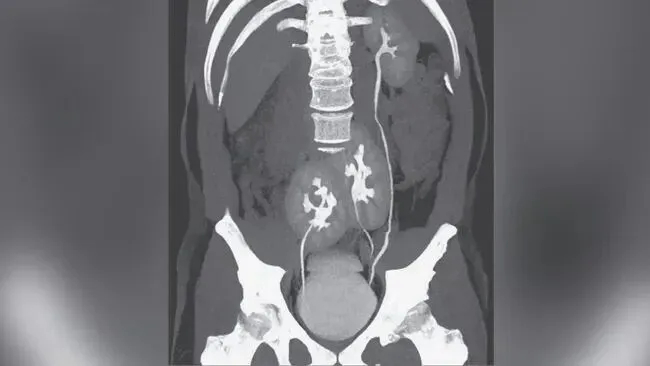

Qua siêu âm bụng và chụp CT, các bác sĩ phát hiện bệnh nhân có quả thận thứ ba, còn được gọi là "thận thừa". Quả thận thừa này nằm ở bên phải và được nối với quả thận phải ban đầu, tạo thành cấu trúc tổng thể hình móng ngựa.

Tuy nhiên, sự hiện diện của một quả thận phụ có thể làm tăng nguy cơ biến chứng đường tiết niệu trong một số trường hợp nhất định. Trong trường hợp này, các nghiên cứu hình ảnh cho thấy cả hai thận đều bị sưng, kèm theo hình thành sỏi. Sỏi thận là những cấu trúc tinh thể được hình thành khi nồng độ khoáng chất trong nước tiểu tăng cao. Sỏi nhỏ thường được đào thải qua nước tiểu, nhưng nếu chúng vẫn còn trong thận hoặc niệu quản, chúng có thể gây tắc nghẽn và thúc đẩy nhiễm trùng.

Trong trường hợp này, nhiễm trùng thận trái của bệnh nhân nghiêm trọng hơn, và có sự tích tụ sỏi trong niệu quản nối thận trái với bàng quang, cho thấy sự tắc nghẽn đường tiết niệu. Tắc nghẽn đường tiết niệu .Điều này có thể dẫn đến ứ đọng nước tiểu, tạo môi trường thuận lợi cho sự phát triển của vi khuẩn. Tình trạng "tắc nghẽn và nhiễm trùng chồng chéo" này được coi là yếu tố chính làm tình trạng bệnh nhân xấu đi. Cần lưu ý rằng thận phụ thường không trực tiếp gây ra nhiễm trùng đường tiết niệu, nhưng các bất thường về mặt giải phẫu đi kèm, chẳng hạn như khả năng thoát nước tiểu kém, có thể làm tăng nguy cơ sỏi và tắc nghẽn đường tiết niệu, từ đó tạo điều kiện cho vi khuẩn phát triển. Trong trường hợp này, sỏi và tắc nghẽn nhiều khả năng là nguyên nhân trực tiếp làm tình trạng nhiễm trùng xấu đi, trong khi thận phụ chỉ là một yếu tố tiềm ẩn.